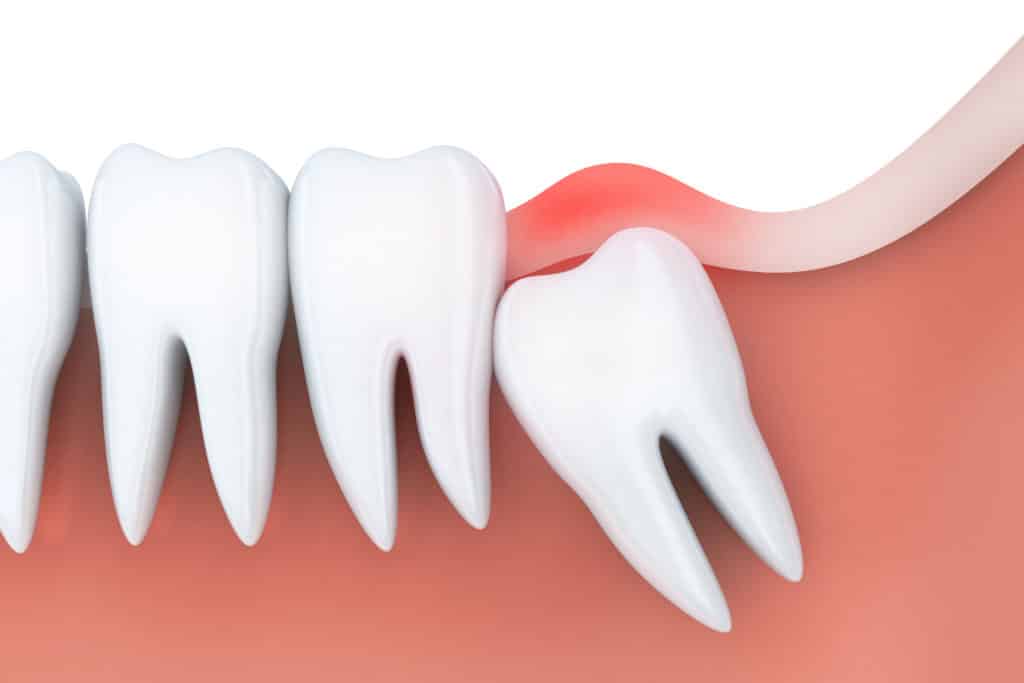

- Răng khôn mọc lệch

- Hướng mọc lệch ra má hoặc vào trong.

- Nếu không gây sưng đau hay viêm lợi, có thể chưa cần nhổ.

- Nếu kèm triệu chứng như lợi trùm, sưng nướu, đau nhức, bác sĩ tại YEN DENTAL sẽ thăm khám và đưa ra phương án điều trị phù hợp.